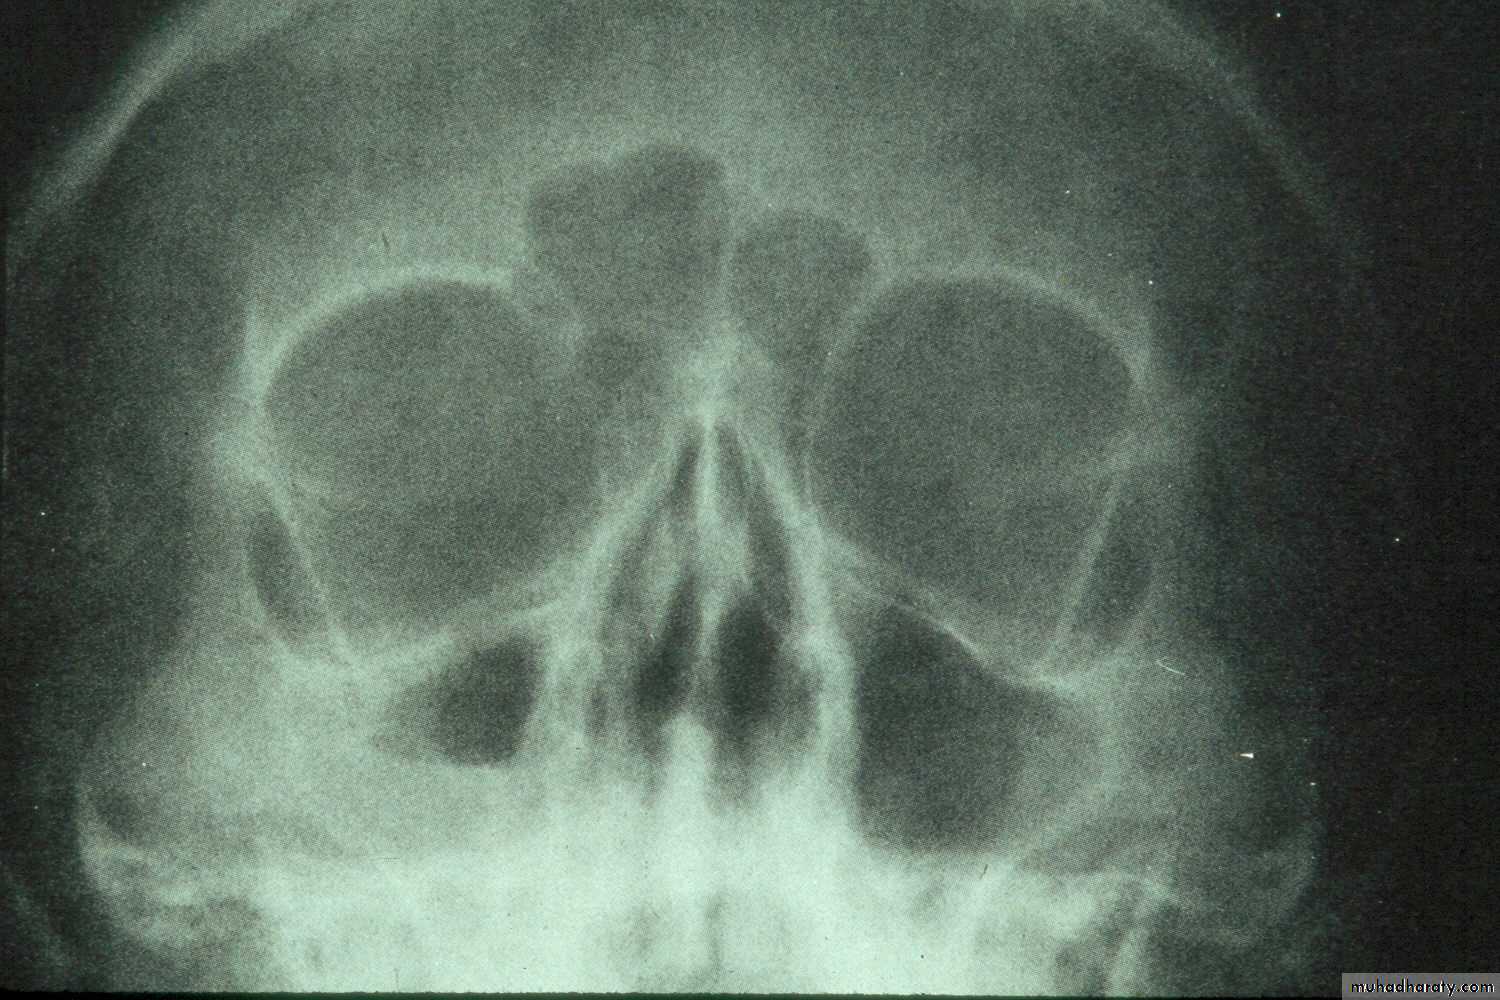

d. Occipitofrontal View: Is recommended to detect multisinusitis,

Hypoplastic left frontal sinus and nosocomial right maxillary sinusitis